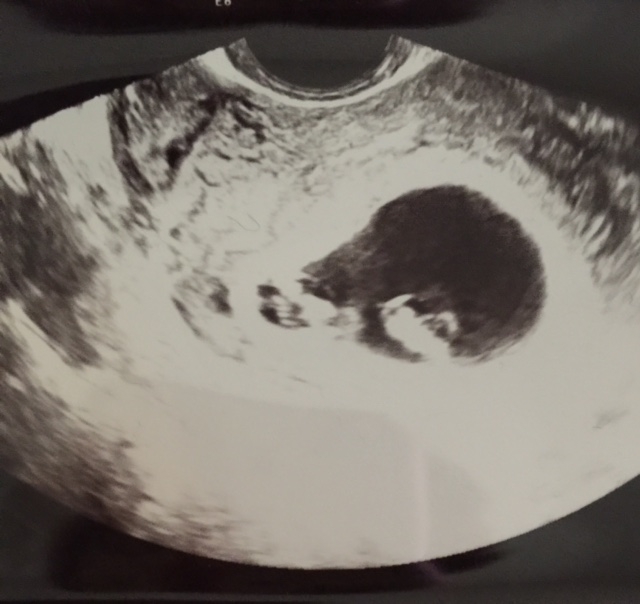

FINALLY!!!! Got to see our little jelly bean! Measuring 7 weeks on the dot and heart rate was strong 137!! So in love and it definitely has made reality set in!